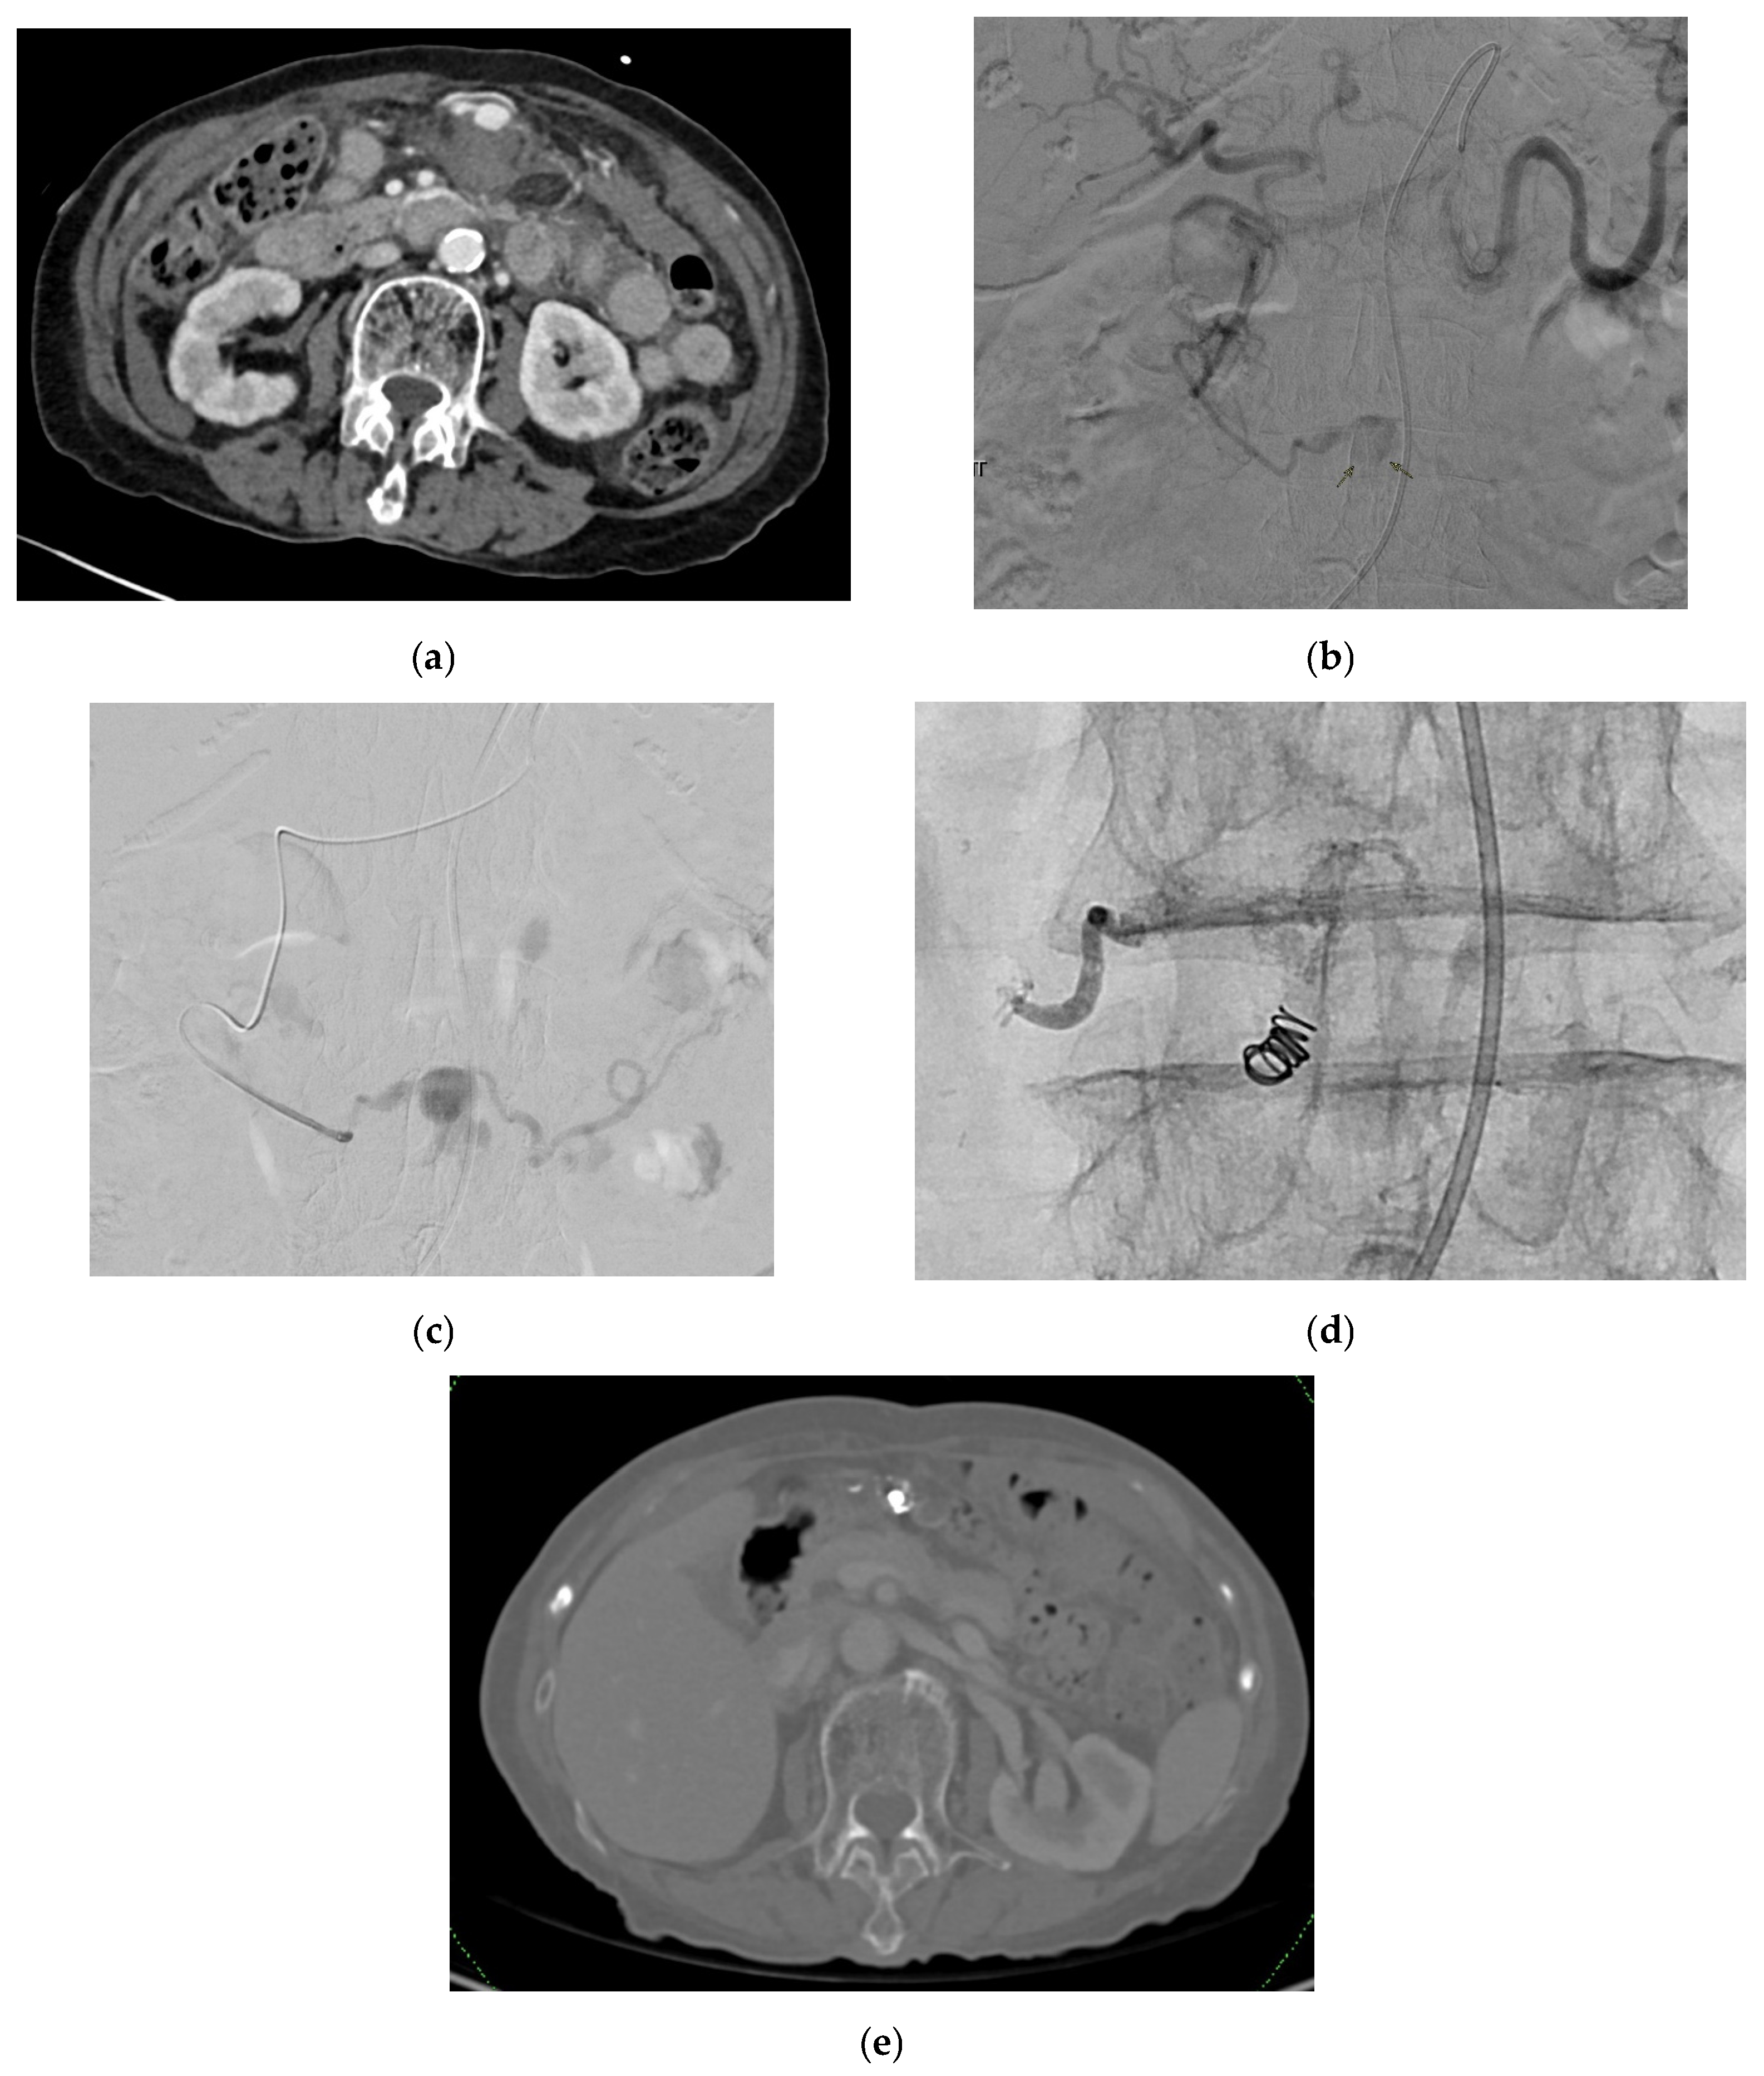

3.1. Superior Mesenteric Artery

3.1.4. Diagnosis

3.1.5. Management